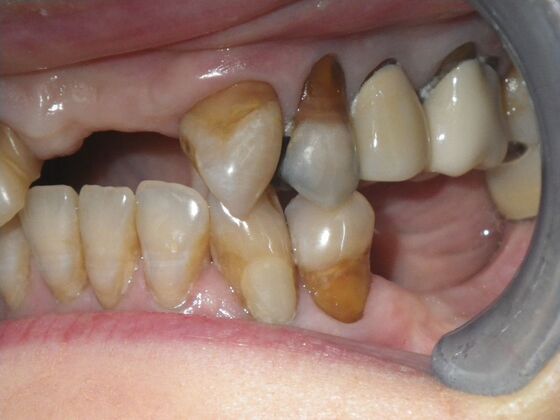

Cosmetic Changes with Veneers and Crown and Bridge: Case 6

Description

This patient had long term acidic erosion of upper and lower teeth eventually leading to loss of upper left central and lateral incisors. While she was somewhat happy with replacement of her front teeth with a removable appliance, she really desired to have something she didn't have to remove. So patient opted to be conservative with two single unit crowns as well as a four unit anterior bridge. These were fabricated using all ceramic without metal